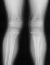

X-ray Set 1. 10 Months post Fracture, Right 8* Left 19* Mechanical axis